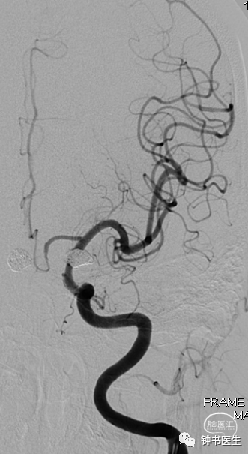

68岁女性,双侧后交通动脉瘤栓塞术后6年

2015-06-26,蛛血,DSA示双侧后交通动脉瘤,左侧为责任动脉瘤,行支架辅助左侧后交通动脉瘤栓塞(LVIS 4.5-20,8枚弹簧圈)。

2015-11-03行右侧后交通动脉瘤LVIS+弹簧圈栓塞,左侧动脉瘤瘤颈残留,未处理。

2018-06-06左侧后交通动脉瘤Pipeline 4025植入。